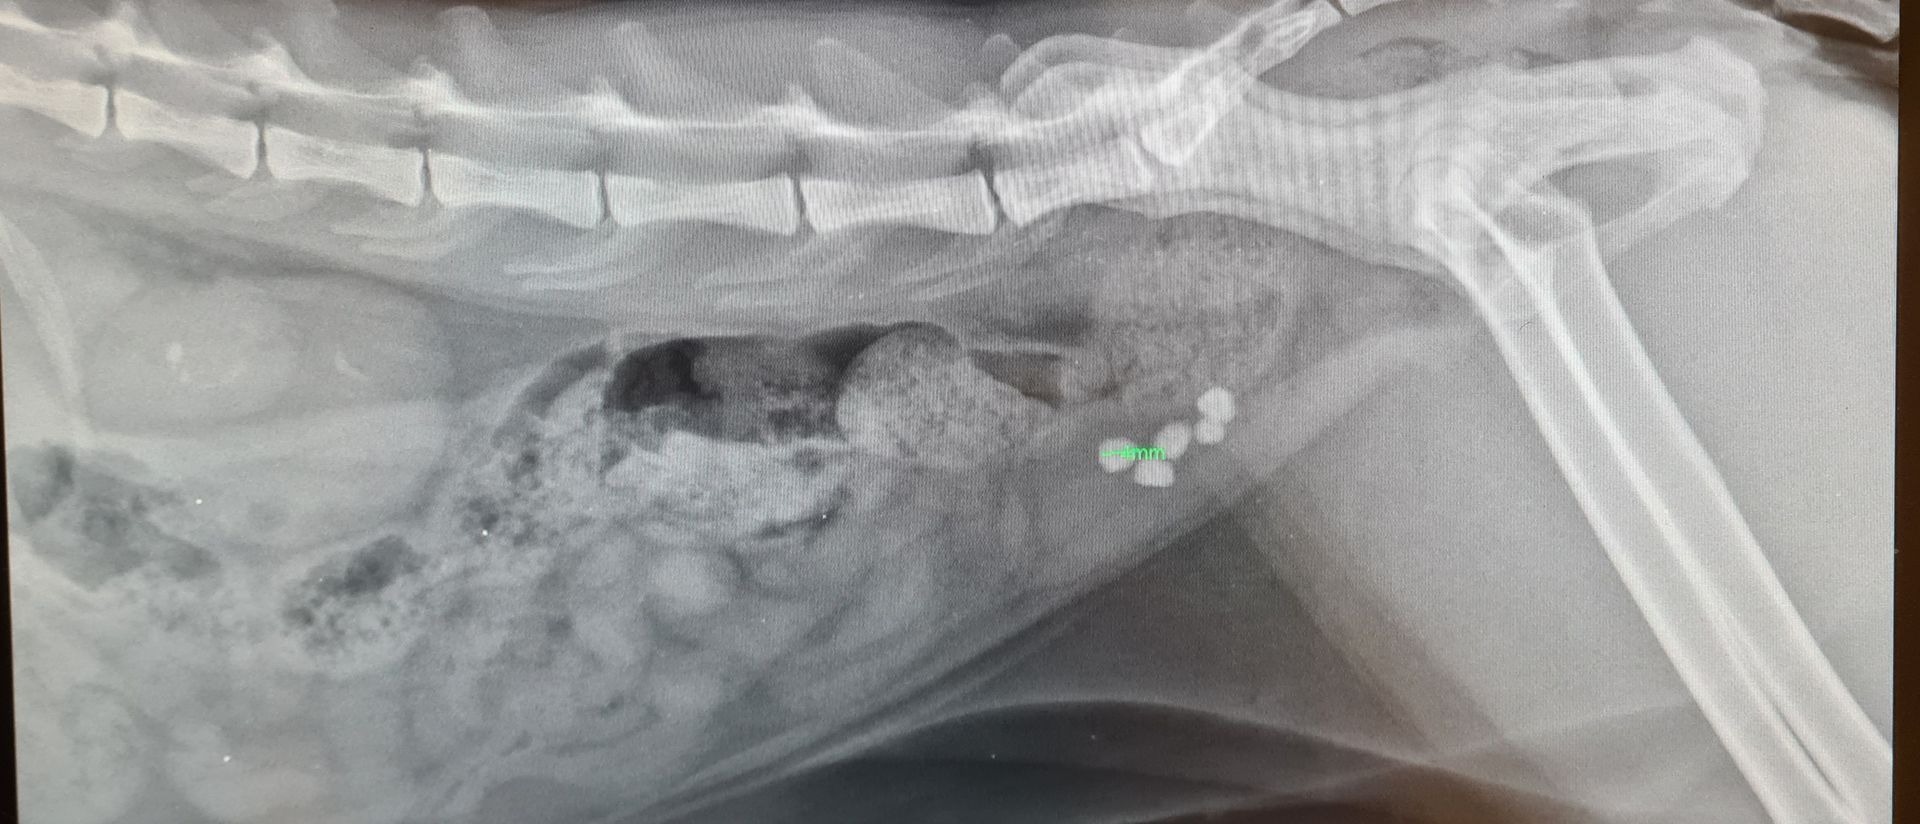

La radiologie

La clinique est équipée d'un générateur radio ainsi que d'un développement numérique. Ce type de développement est rapide, sans utilisation de produits chimiques et permet d'obtenir les images sur un écran d'ordinateur. La définition des radios est ainsi meilleure. Nous pouvons aussi facilement vous faire parvenir les radios de votre animal ou les transférer à un confrère le cas échéant par mail.

- Radios classiques

- Radios avec produit de contraste